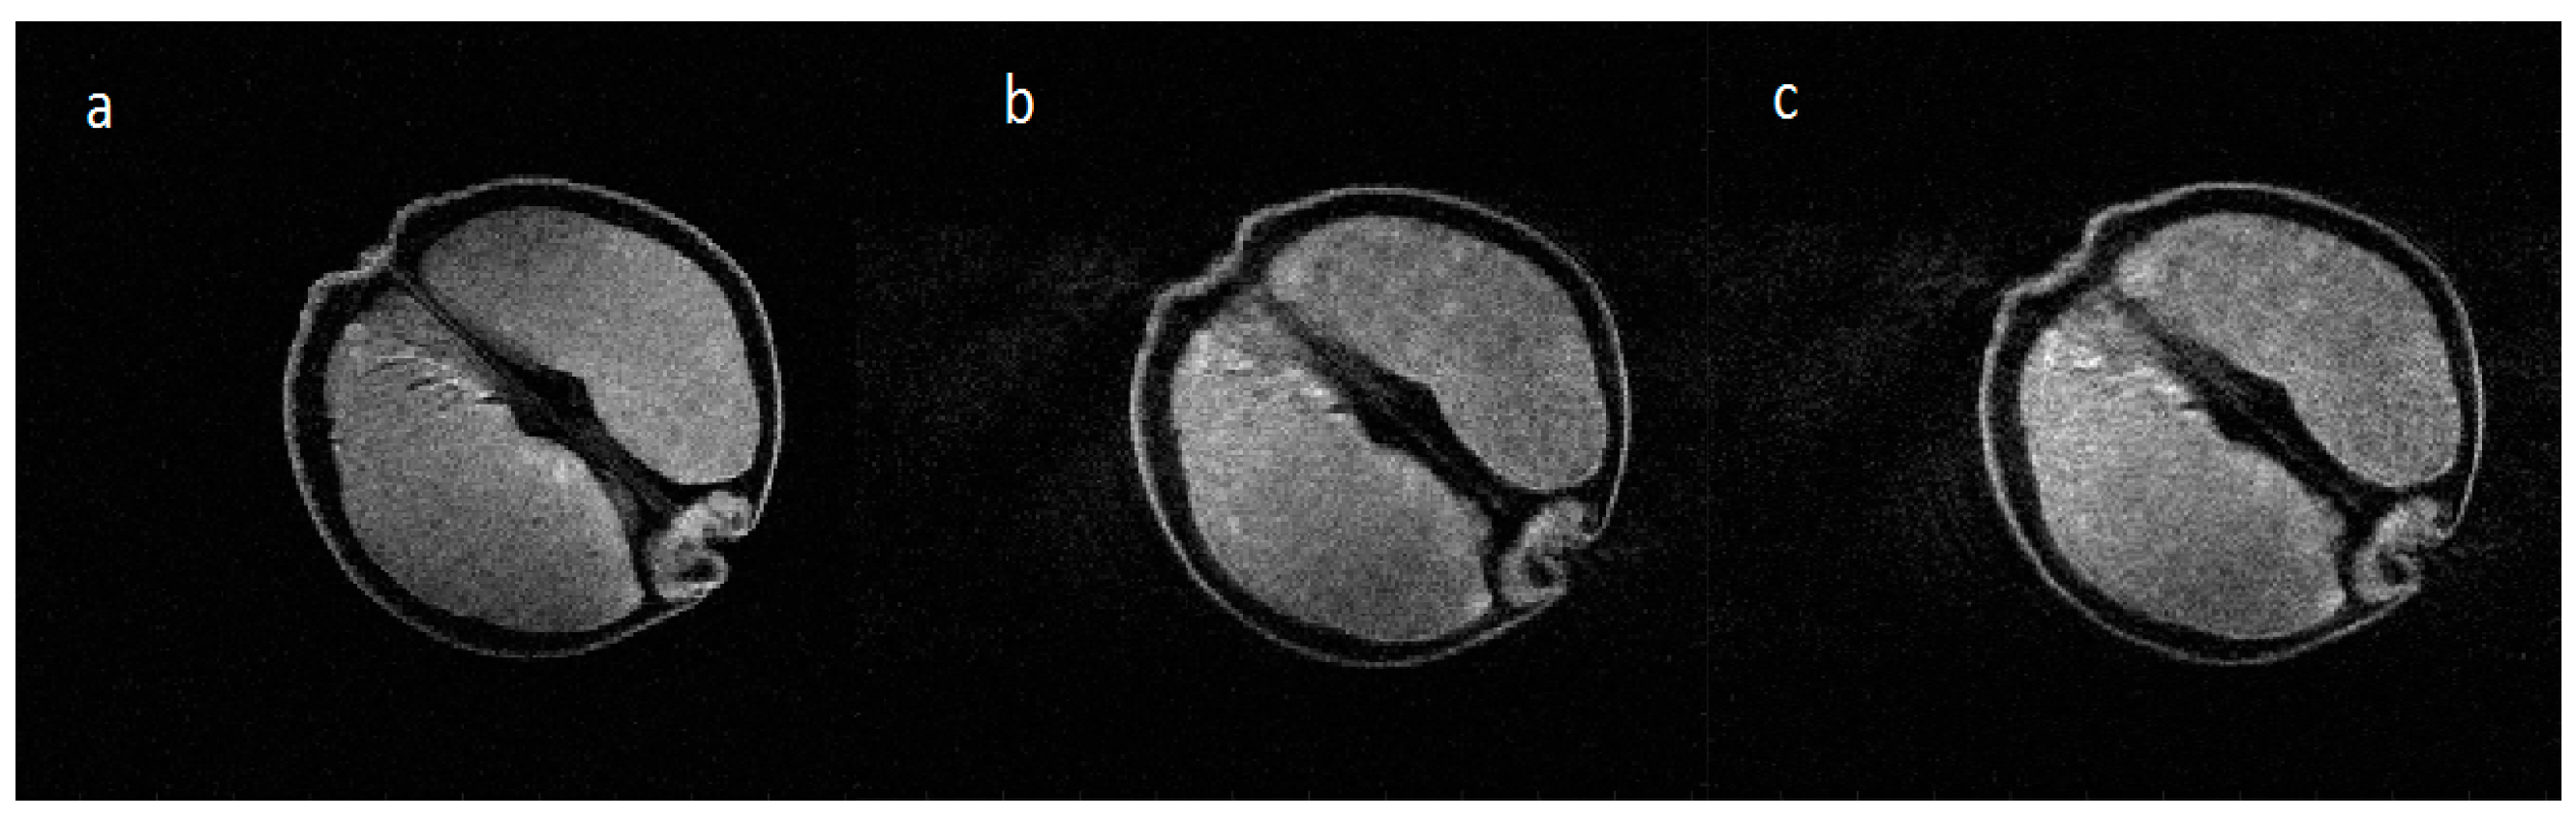

Images acquired with approximately five times more angular motion (2 × 10−1 radians), similar to the simulation shown in Figure 6e, are shown without and with motion in Figure 9a,b respectively and the result of the motion correction algorithm is shown in Figure 9c. The effects of the correction on the original k-space data are shown in Figure 9d–f. It can be seen that several offset k-space lines have been reassigned after the correction, although the overall correction still shows considerable artifact.

The red arrow on Figure 9c illustrates improved left edge definition produced by the correction. The large spikes offset from the center of k-space by motion seen in Figure 9e are removed by the correction algorithm as shown in Figure 9f but serious phase errors still remain in the data set causing residual ghosting.

Figure 9. MR images with no in-plane angular motion (a); and pseudo-sinusoidal motion (b); In (c), an attempt to remove the motion using the measured angles shows some improvement of the k-space data as can be seen by comparing (df) where the individual k-space lines are plotted together.